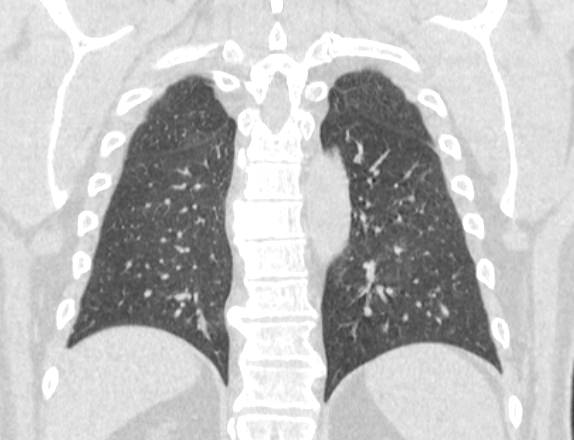

Мультиспиральная компьютерная томография органов грудной клетки представляет собой рентгеновское исследование костных структур грудной клетки, легочной ткани, бронхиального дерева, органов средостения.

Информативность МСКТ органов грудной клетки дополняет функциональная проба, то есть методика проведения сканирования на вдохе (инспираторная КТ) и на выдохе (экспираторная КТ). При выполнении КТ на вдохе с задержкой дыхания удается добиться максимального контраста между наполненными воздухом легкими и более плотными структурами, такими как плевра, стенки бронхов и кровеносные сосуды. Кроме того, на фоне пневматизированных легких хорошо видны очаговые и диффузные патологические изменения.

При экспираторной пробе (пробе на выдохе) можно выявить воздушные ловушки (то есть стойкое повышение пневматизации легочной ткани) на фоне пневмонитов, бронхиолитов, обструктивных заболеваний легких, эмфиземы.

Компьютерная томография в нашей клинике проводится на современных мультиспиральных томографах, которые производят тончайшие срезы исследуемой области и создают трехмерные изображения всех структур грудной клетки высокой четкости и контрастности. Увеличенное количество детекторов, которыми оснащены аппараты, обеспечивают быстрое сканирование зоны исследования при минимальных дозах рентгеновского облучения.